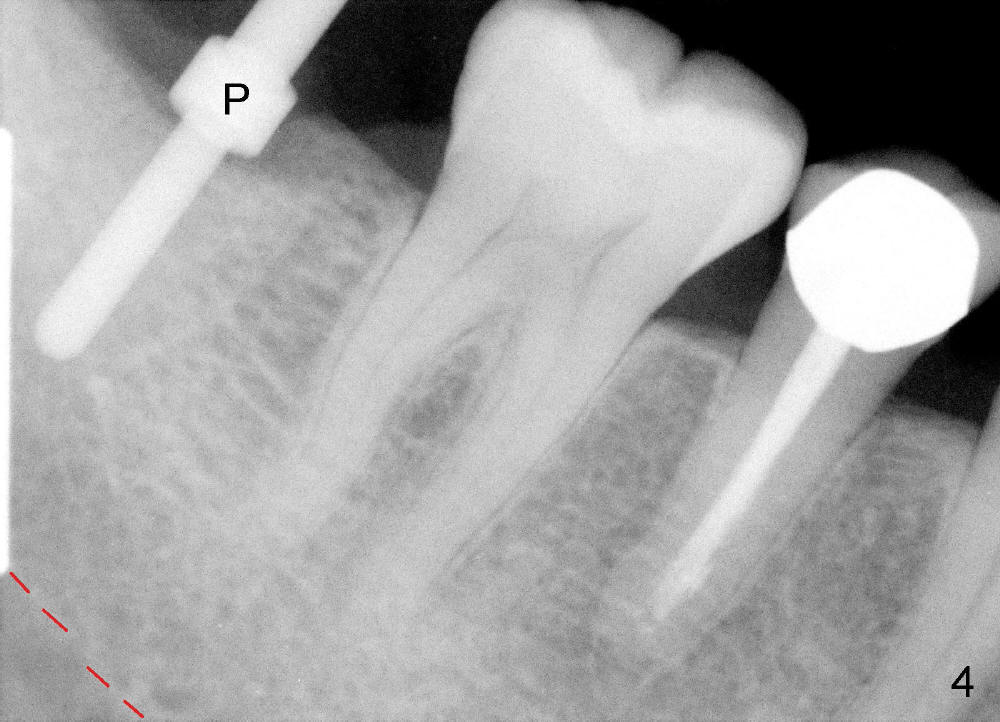

Infiltration anesthesia is administered with 68 mg of Septocaine, 34 mg of Lidocaine, 34 mcg of Epinephrine around the site of the lower right 2nd molar. An incision is made. A 2 mm pilot drill is used to initiate osteotomy at the depth of 8 mm. A parallel pin is inserted for the 1st intraop PA (Fig.4: P), which shows once more time the likelihood of incooperation from the patient. Combined with the information from CT, it appears alright to continue increasing osteotomy in the diameter and depth until 5x11 mm (Fig.5,6 (T: tap)). A 6x14 mm tap is inserted at 11 mm in bone. When the tap is removed, an explorer is used to check the intrigity of the osteotomy walls. No vibration is palpated linguoapically during drilling and inserting taps. There is no abnormal hemorrhage from the osteotomy. Finally 6x14 mm implant is placed as expected (Fig.7). The wound is healing 6 days postop (Fig.8).